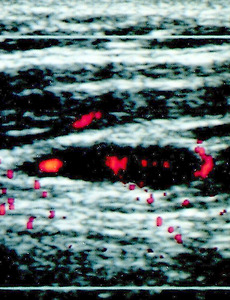

percutaneous ethanol injection,pei,sono guide Fig. 5C. —Persistent perfusion after initial percutaneous ethanol injection requiring retreatment in 36-year-old man with papillary thyroid carcinoma. Longitudinal sonogram obtained 9 weeks after percutaneous ethanol injection shows size of lymph node is unchanged, and there is evidence of slight residual perfusion. Because of these findings, percutaneous ethanol injection treatment was repeated. 2012. 12. 8. 이전 1 2 다음